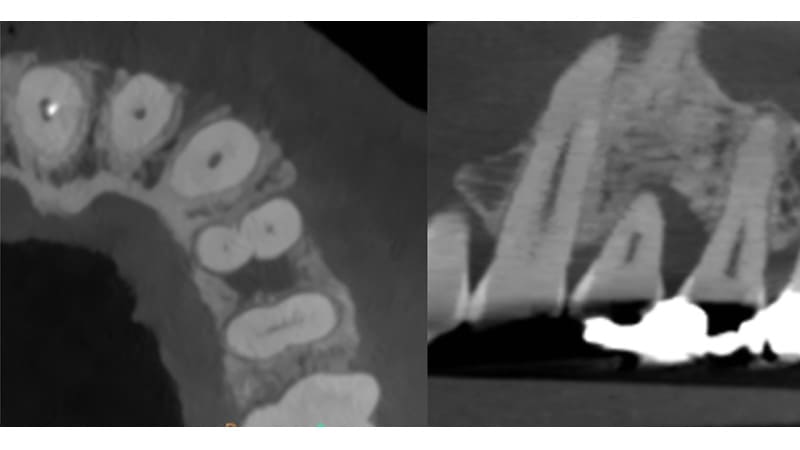

症例①:右下の奥歯が腫れる

| 治療科目 | 歯周組織再生療法(リグロス使用) |

|---|---|

| 主訴 | 右下の奥歯が腫れる |

| 治療期間 | 1年 |

| 治療費 | 2〜3万円程度 |

| 治療内容 | 浸潤麻酔後、歯肉を剥離し歯石除去する。リグロスを塗布し緊密に縫合。3ヶ月後に再評価。 |

| 治療のリスク | リグロスの特性上かなり腫れることがあります。 まれに脂肪腫をつくることがあります。 角化歯肉の状態により再度感染を起こす可能性があり、遊離歯肉移植の併用が必要なこともあります。 清掃方法によって再感染する可能性があり、定期的な通院でチェックしていく必要があります。 |